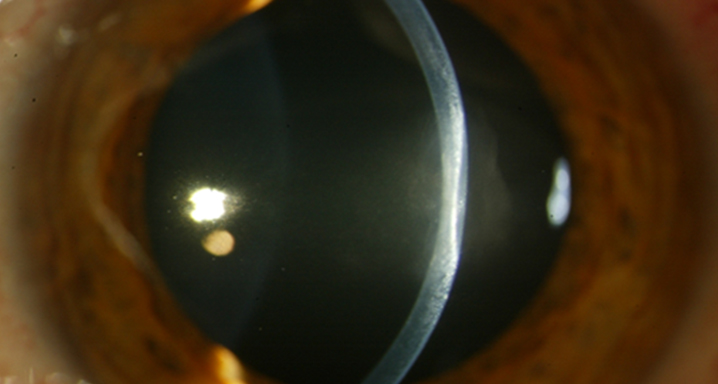

— Queratitis estromal: se produce cuando la infección afecta a las capas más profundas de la córnea y origina un edema estromal, normalmente manteniendo el epitelio intacto, lo que se traduce en disminución de visión, fotofobia y dolor.

— Iridociclitis: puede producirse una inflamación de la cámara anterior del ojo que puede asociarse a una presión intraocular elevada. Causa hipersensibilidad a la luz, visión borrosa, dolor y enrojecimiento ocular.